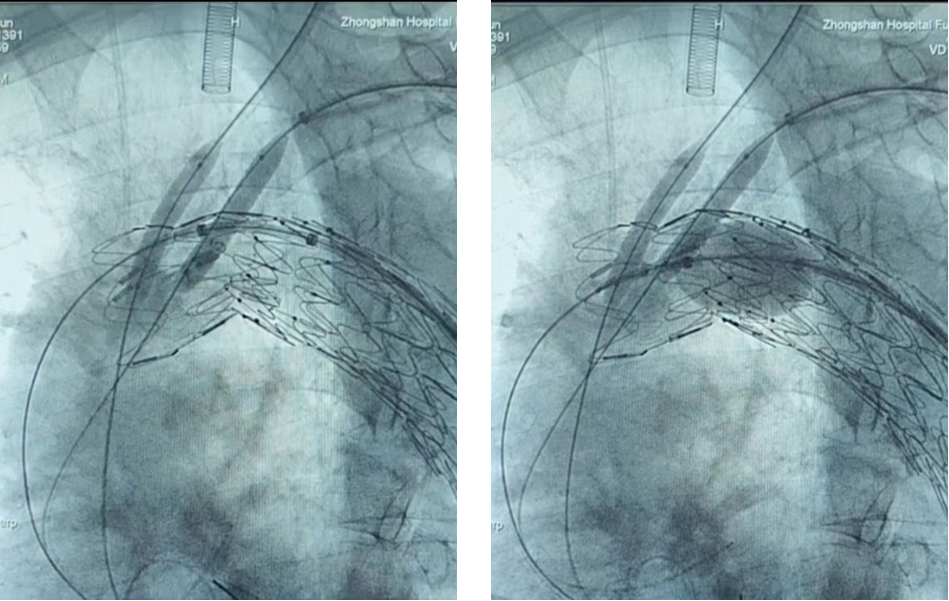

病例三(开窗结合双内分支)

王X,男,57岁,主动脉弓动脉瘤。LSA、LCCA双内分支, IA开窗。

术前

术中